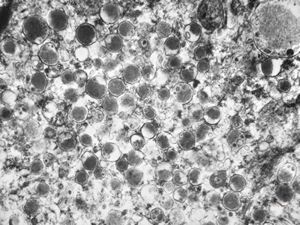

lipid malabsorption

jejunum … lipid malabsorption

F,8m. | lipid malabsorption - large lipid droplets in enterocytes … semithin section

lipid malabsorption - large lipid droplets in enterocytes … semithin section

lipid malabsorption - large lipid droplets in enterocytes and propria … HE